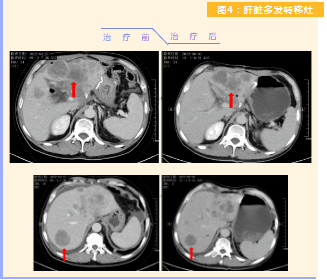

患者完成1周期治療后,上腹部疼痛癥狀基本消失,梗阻性黃疸癥狀緩解,腫瘤指標下降(圖1),肺部多發(fā)轉(zhuǎn)移灶消失和縮?。▓D2),雙肺門淋巴結(jié)縮?。▓D3),肝臟多發(fā)轉(zhuǎn)移灶縮小(圖4)。